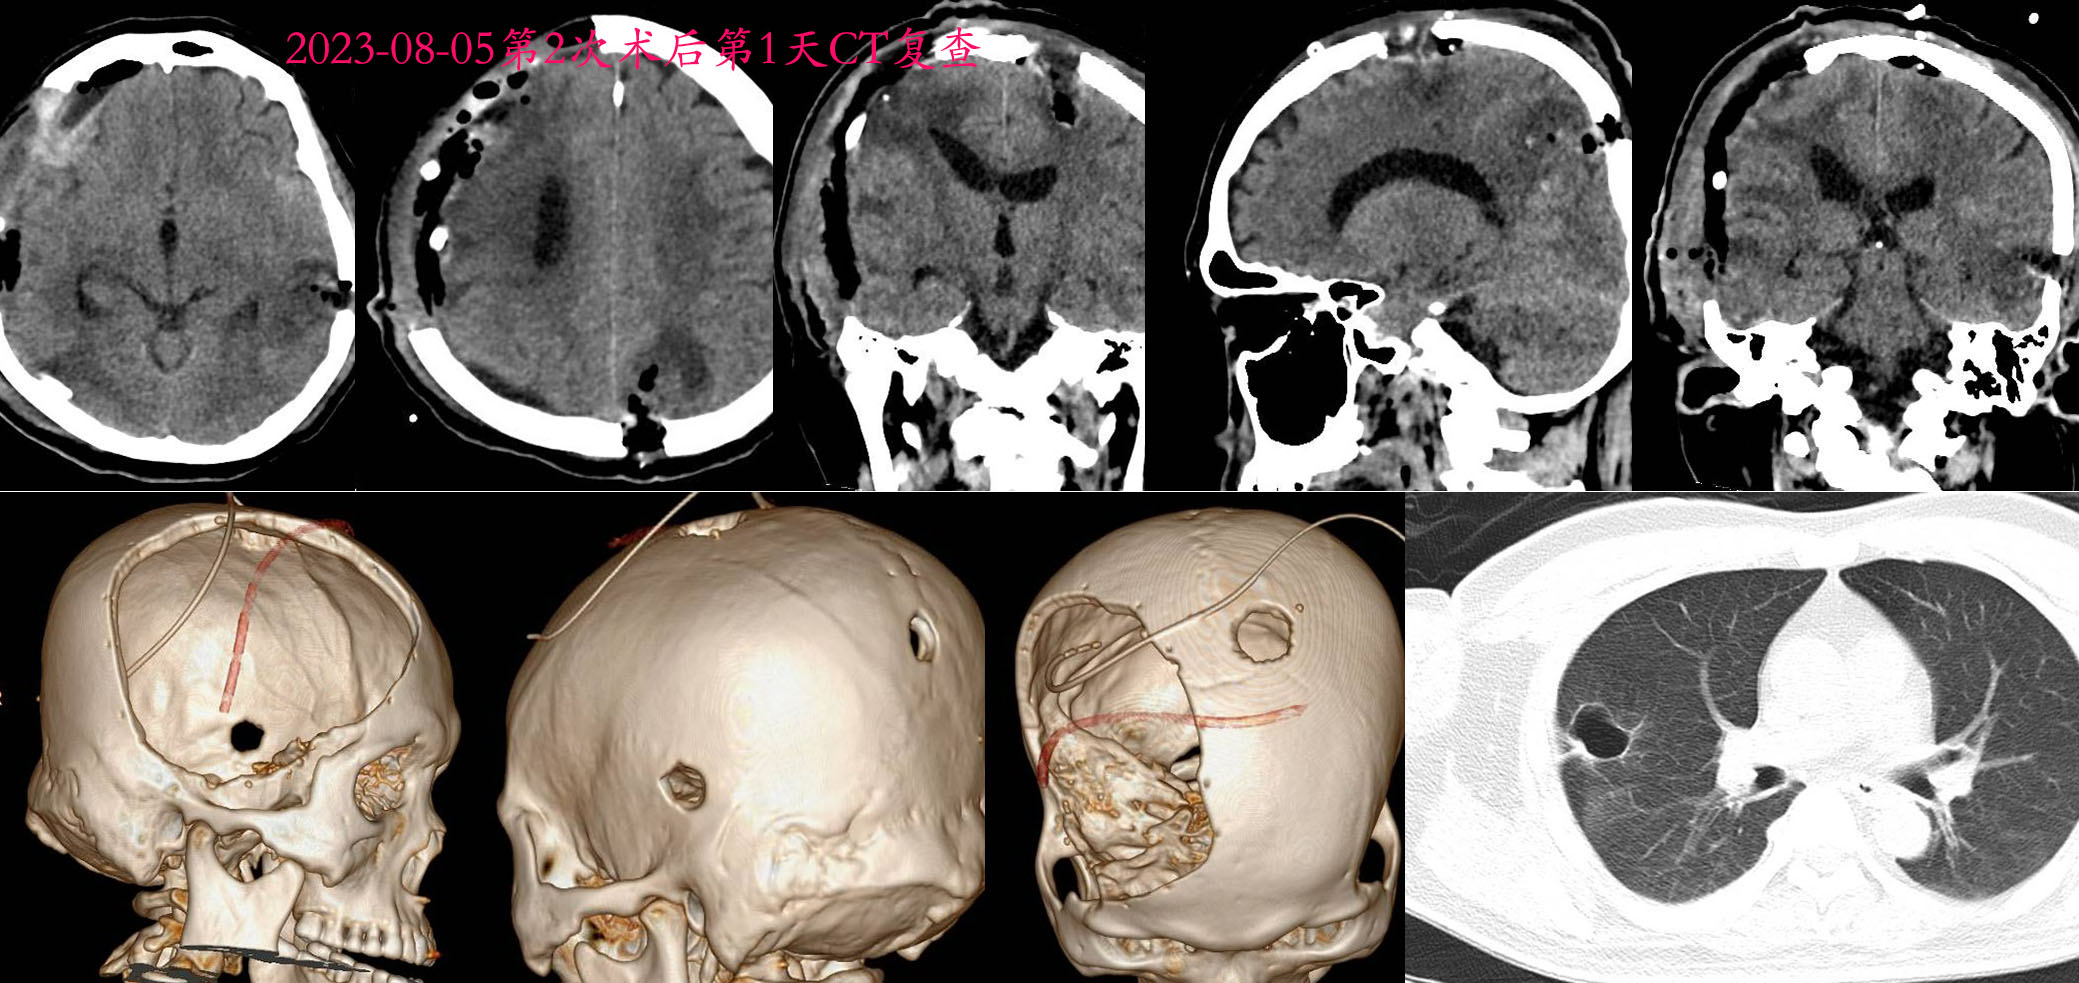

2023-08-05术后第1天CT。

2023-09-05出院时CT复查,可见CT显示肺部病灶明显缩小,考虑肺部脓肿,而非肺癌。患者出院时清醒,但肢体偏瘫,头皮切口尚未完全愈合,转康复医院继续康复治疗,随访3个月后清醒,拔除气管套管,能够讲话。